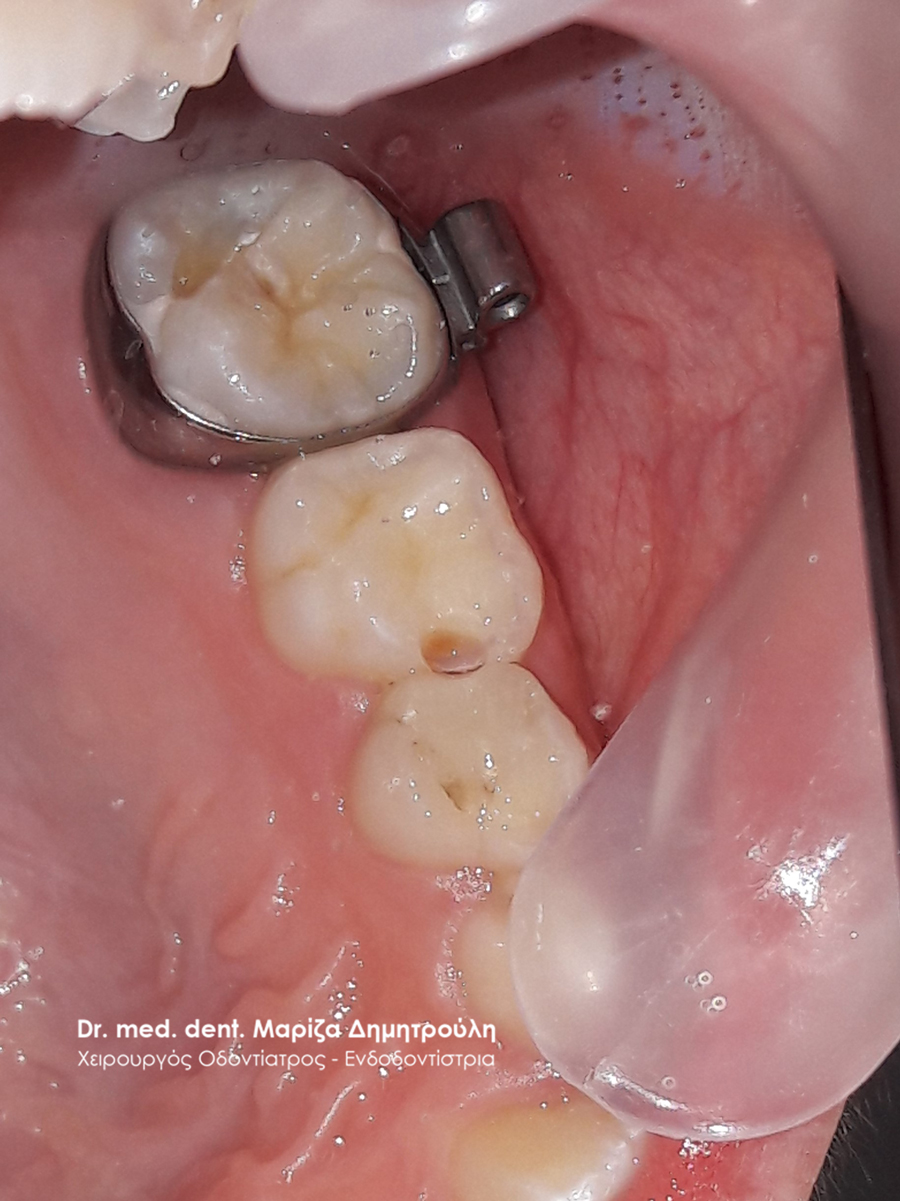

Dental filling of primary tooth

BEFORE

AFTER